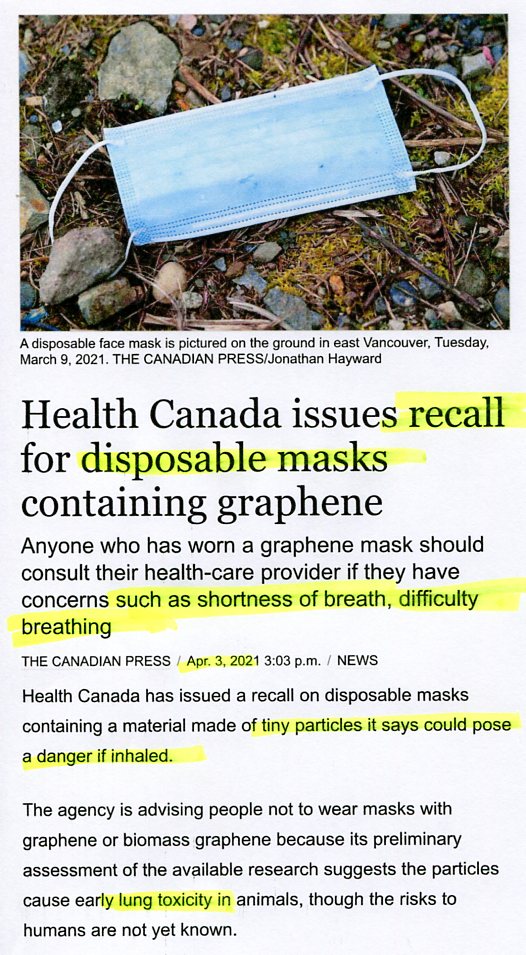

Canada recalls masks causining lung toxicity when breathing

listen Dangerous Hazardous Chemicals in Face Masks

watch Nano-Worms in Face Masks Under Microscope listen

SELF-SUFFOCATING SPIT-MASKS TORTURE

(oxygen-deficient germ-generating atmosphere)

SELF-SUFFOCATING SPIT-MASKS TORTURE